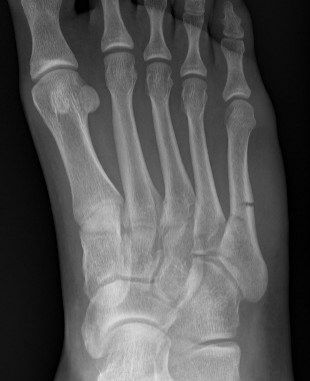

Xray

Zone 2 fractures